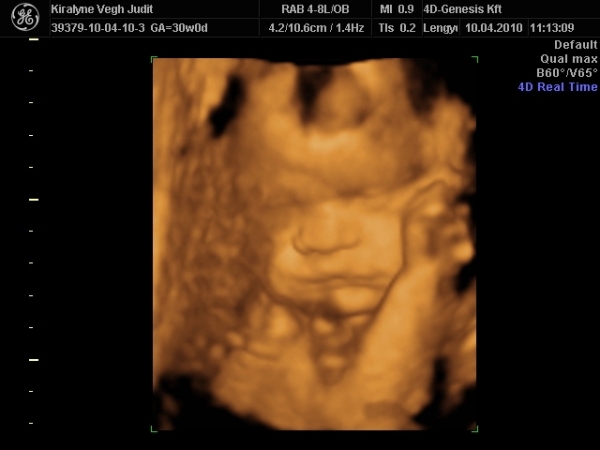

4D-re holnap megyünk 11-re, utána meg tervezünk egy kis csavargást. :lol: :lol: :lol:

Ma jól elfáradtam. Voltunk 4D-n, a várban és a Csodák palotájában. Rengeteget sétáltunk, nem érzem a lábamat.

A lényeg, hogy Izi baba nagyon jól van,

Babócám fejjel lefele, idézem: "méhlepény olyan távol van a méhszájtól, mint Makó Jeruzsálemtől." :oops: :oops: :oops:

Szóval nem értem a szerdai uh-ot. :oops: :oops:

"0" fokban érett a lepény, 1741g kis csöppségem, combcsont mérete alapján már 32 hetesnek felel meg. Amúgy minden mérete alapján 1 héttel idősebb. Magzatvíz átlagos. És tiszta apja. :lol: :lol: :lol: :lol:

És a képek.